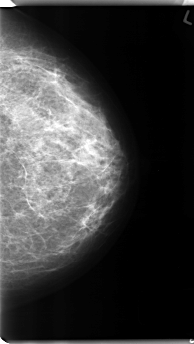

C_0136_1.RIGHT_CC

RIGHT_CC LINES 4712 PIXELS_PER_LINE 2768 BITS_PER_PIXEL 12 RESOLUTION 50 NON_OVERLAY